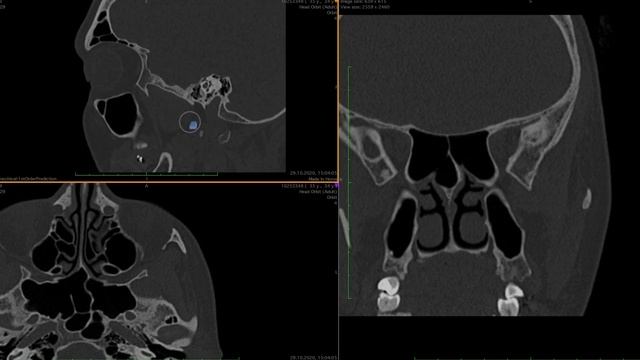

В этом видео мы продолжим разговор о крылонебной ямке. Детально обсудим все сообщения каналы отверстия щели крылонебной ямки с прилежащими анатомическими зонами. Более того мы сделаем это на основе КТ исследования для лучшего понимания и закр..., видео от 2024-01-02 загрузил на rutube Тренировочный вызов...